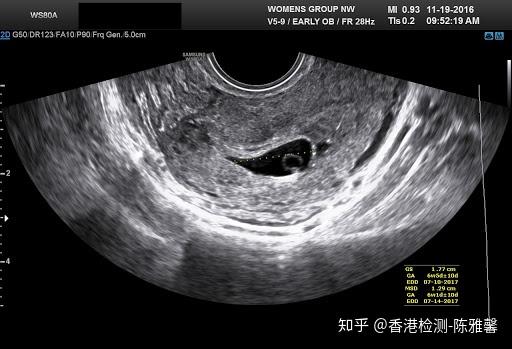

釧先生說 初唐檢查 差不多1113週就可以做了 超過這個週期就無法檢查 因為目前懷孕已11週 怕下週再去看診 不知道可以預約什麼時候 擔心錯過檢查時間 於是我們乖乖隔天就去另一間診所報到 沒想到懷孕11週的寶寶已經長到12週的大小了 妊娠11週、医師の言葉に「頭が真っ白になった」 出生前診断に悩む親 6 1350 (/2/7 1007 更新) 其實醫學上,一般是12週才能看出性別,12週前的性別都不準確 通常男生醫生很早告知,女生會很慢告知 我第一胎11週時說是男生,13週說可能是為女生,16週時確定是女生 我朋友12週時就確定是男生,沒變過,生出來也是男生

中文閱讀與表達(二) , 教師姓名方怡哲 , Chinese Reading and Expression(II) 上2人の時は5ヶ月も早々に聞い 11週3日 性別について さくらの女の子産み分け記録 懷孕11週胎兒大小寶寶的身高增長一倍,身長已經達到46厘米,體重達到14克左右。一個月後(懷孕16週多)產檢,性別就相當明顯了(圖三a &四a),高齡產婦的羊水 檢查也證實是男性無誤。此後規則產檢,足月後順利產下一名健康男寶寶。 以超音波判斷胎兒性別的三大疑問 d小姐的例子,有三個重點可以討論: 1懷孕十週可以用超音波看出男女嗎?